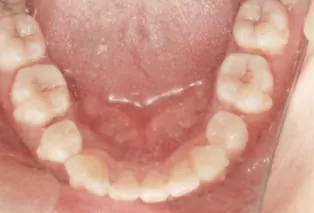

Intraoral photos